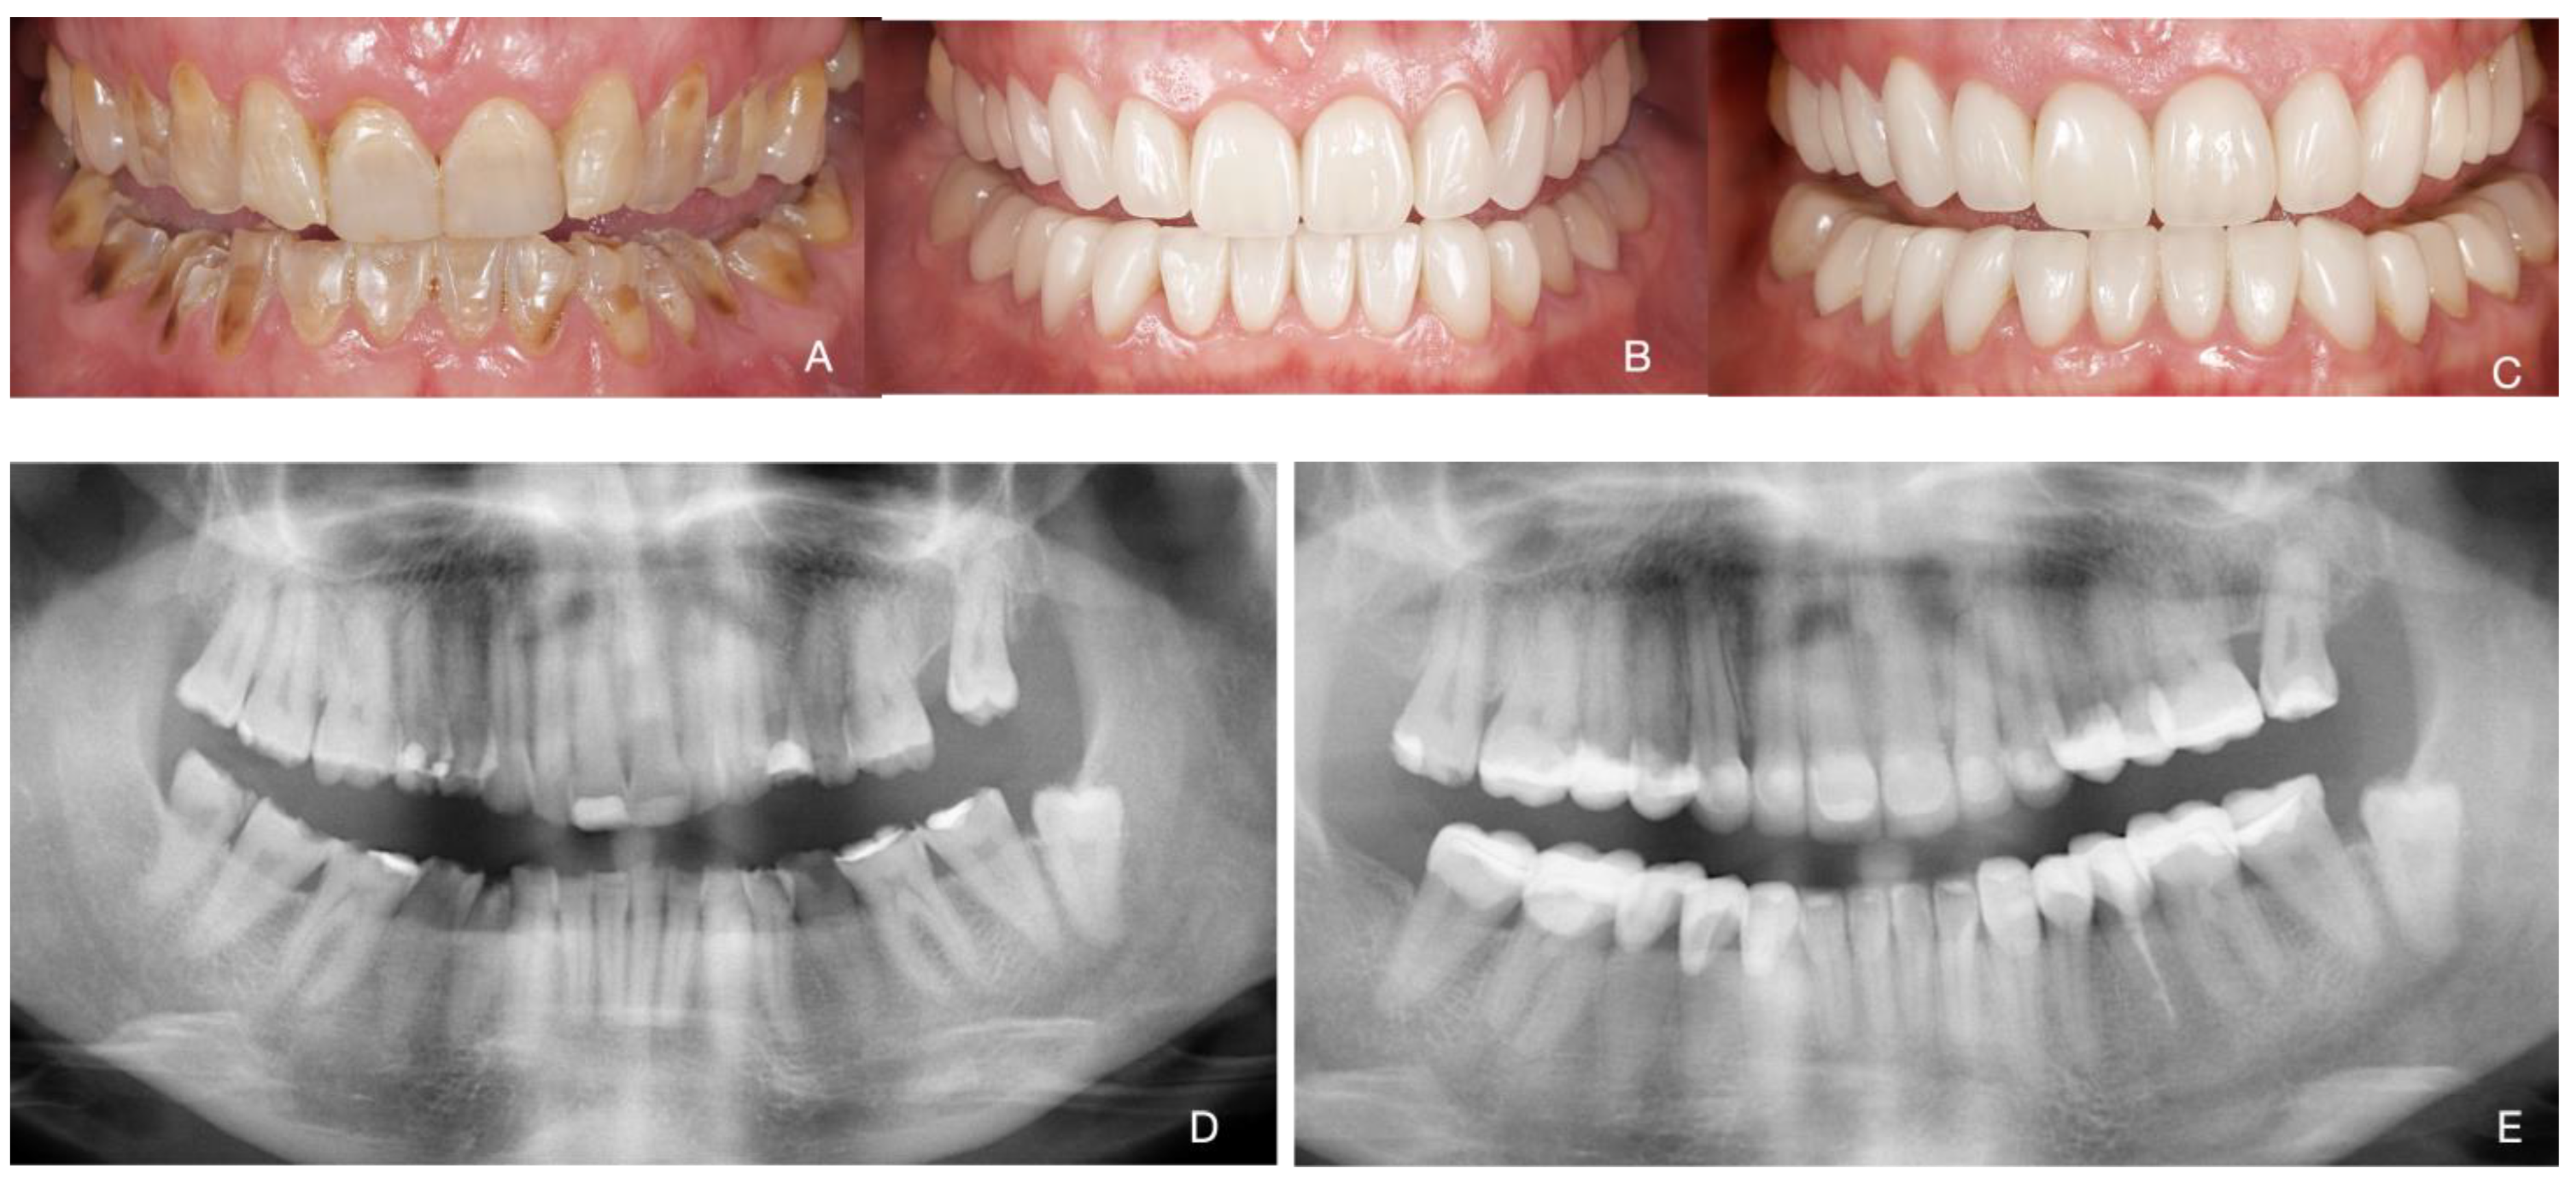

Total Rehabilitation Using Adhesive Dental Restorations in Patients with Severe Tooth Wear: A 5-Year Retrospective Case Series Study

3. Results